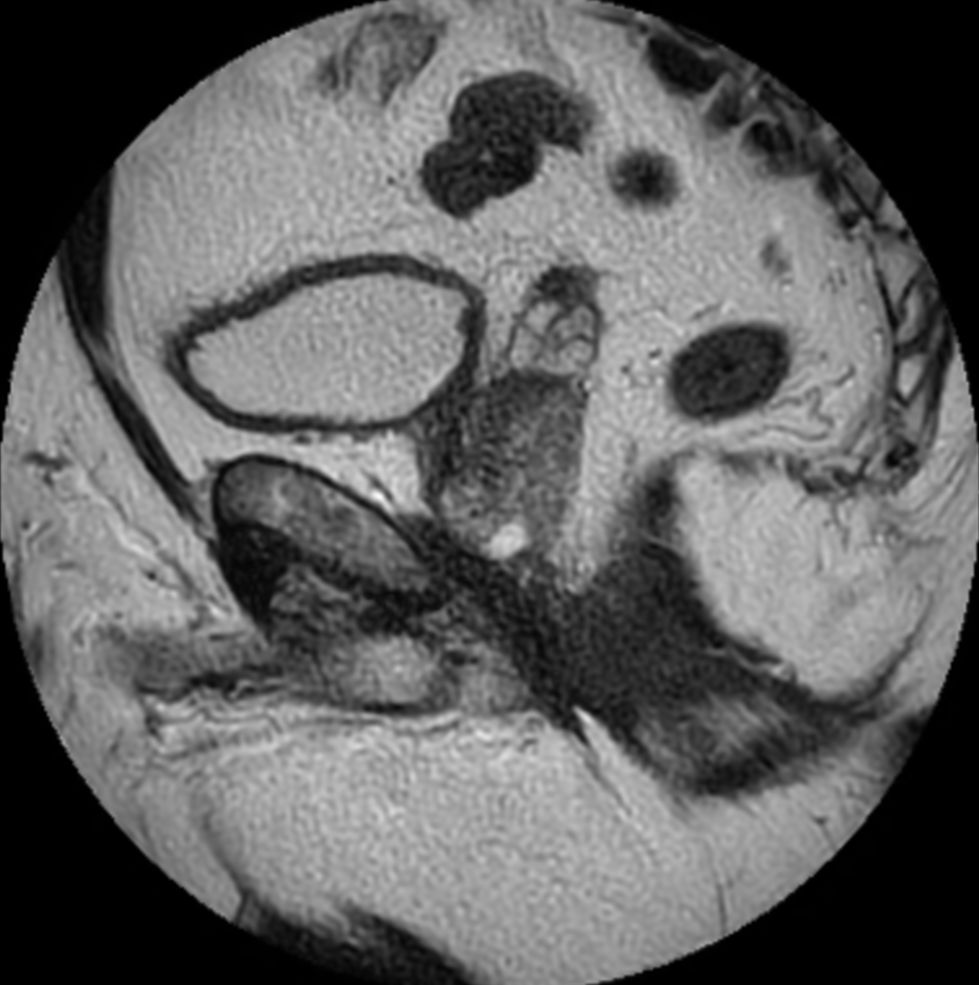

Axial T2w TSE

Axial 3D T2w TSE (PelvisVIEW)

Coronal T2w TSE

Sagittal T2w TSE

Sagittal T2w TSE MultiVane XD